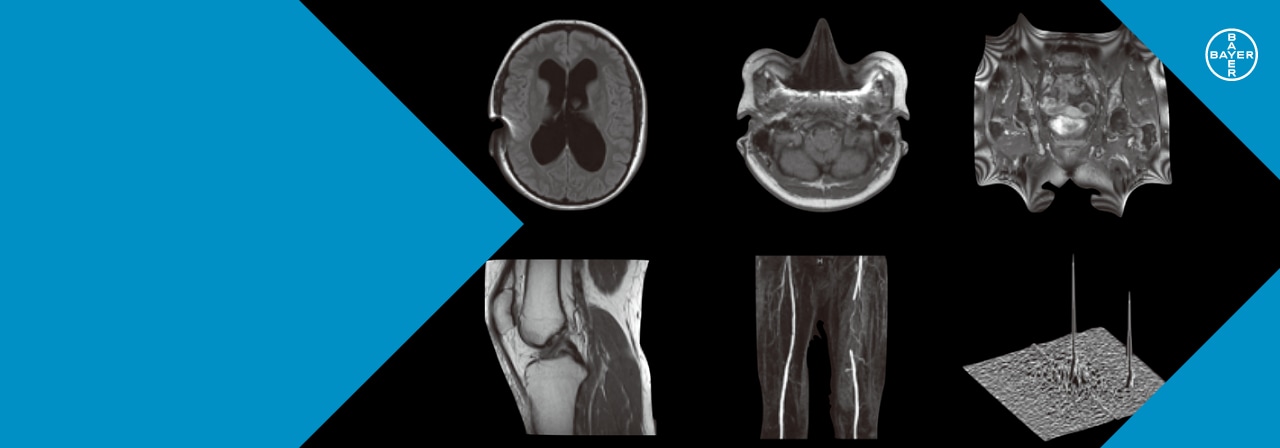

m3.com 電子書籍 | 画像診断 2012年1月号(Vol.32 No.1) MRIアーチファクトの光と影, MRIで生じるアーチファクト | 画像診断情報サイト Bayer in Radiology|医療関係者向け情報,

MRIで生じるアーチファクト | 画像診断情報サイト Bayer in Radiology|医療関係者向け情報, 第10回 MRIの進歩~より早く、より細かく | ナース専科,